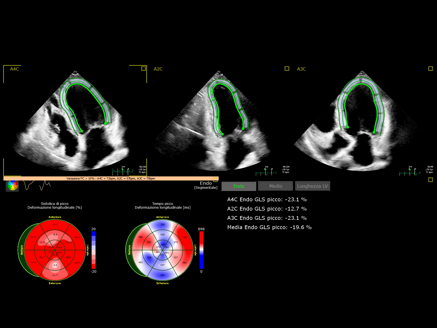

Applicativi avanzati di anali ecocardiografica consentono in maniera non invasiva di ottenere informazioni accurate sulla funzione meccanica del cuore e stime precise anche delle pressioni polmonari.